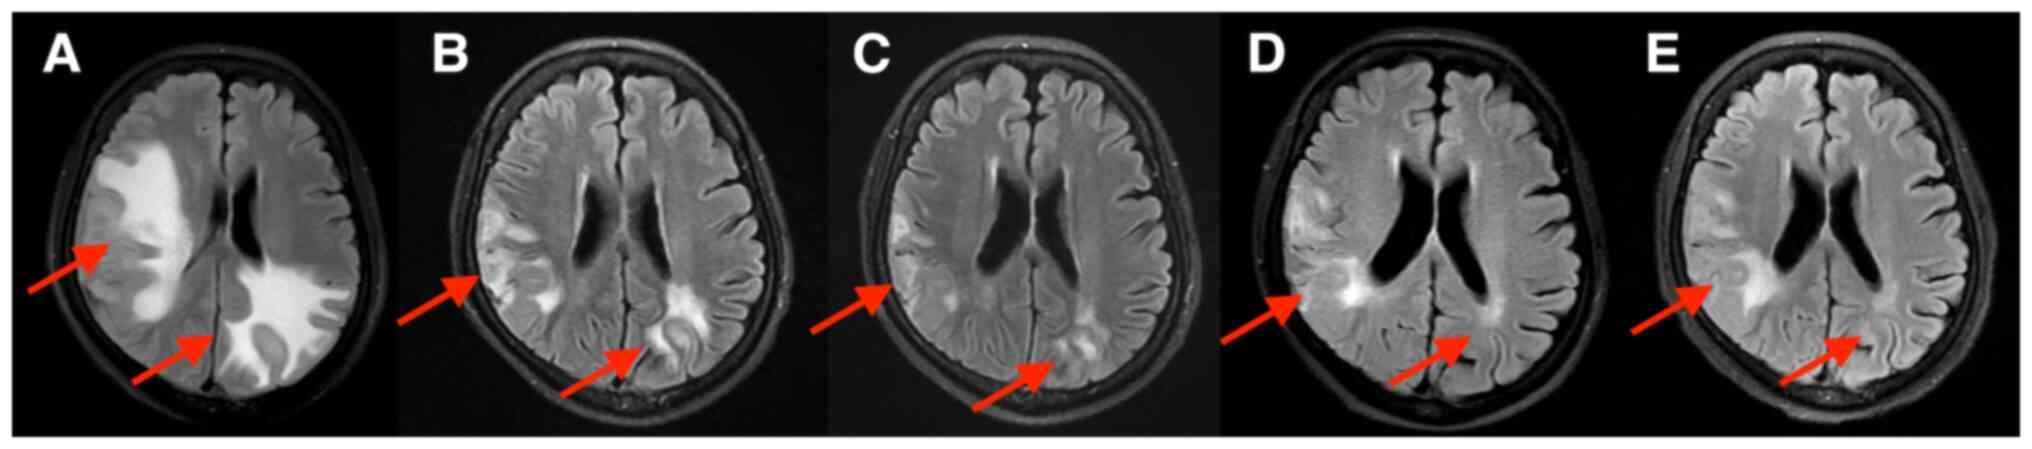

Although human epidermal growth factor receptor 2 (HER2)‑targeted therapy significantly improves the prognosis of patients with HER2‑positive breast cancer, most patients with advanced breast cancer eventually progress due to drug resistance. At present, there is no standard treatment after patients become resistant to HER2‑targeted therapy. Previous studies have indicated that anti‑angiogenesis drugs have potential efficacy in the treatment of advanced breast cancer. The present study reported on a case of a pretreated patient with HER2‑positive advanced breast cancer with brain metastases who developed resistance to multiple lines of HER2‑targeted treatment. The patient was treated with apatinib combined with trastuzumab and albumin‑bound paclitaxel. The patient achieved partial response to the third‑line treatment with a progression‑free survival of 9 months. After combination treatment, the symptoms of headache and vomiting were relieved and all the brain metastases were significantly reduced. The present case indicated that apatinib may have anti‑tumor activity in patients with HER2‑positive breast cancer with HER2‑targeted drug resistance. The present case provides valuable information and may offer a new possibility for the treatment of patients with breast cancer with brain metastases who progressed after clinical treatment with small‑molecule anti‑HER2 tyrosine kinase inhibitor drugs.

Figure 1